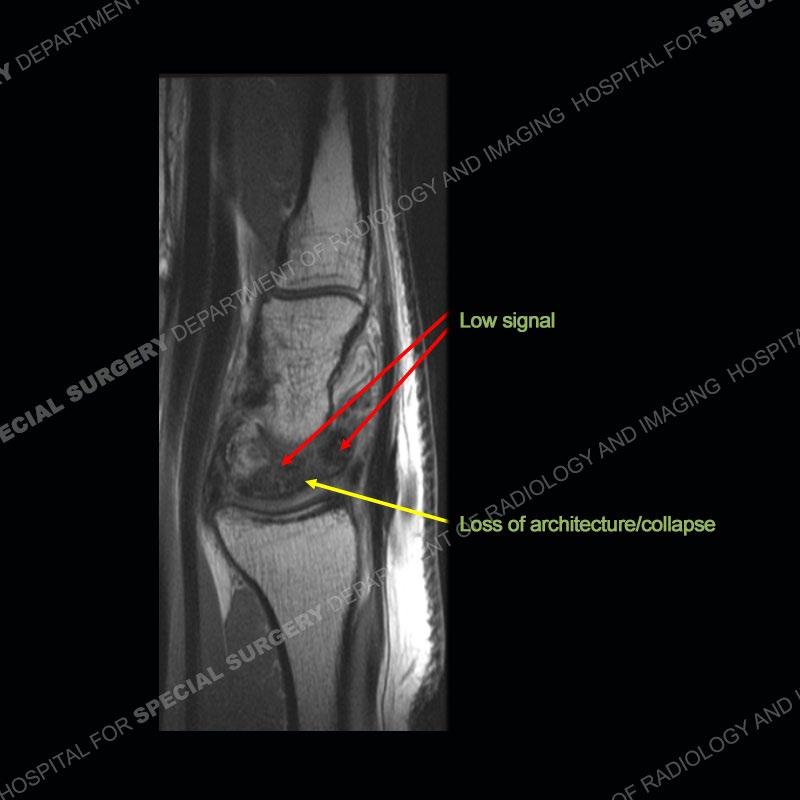

Both cases demonstrate similar findings to slightly less and more conspicuous degrees. The radiographs show sclerosis and fragmentation/collapse of the lunate. The CT images for case one just further clarify the architecture of the lunate. The MRI images show a slightly greater degree of variability but with overall persistent areas of low signal of the lunate on all pulse sequences and with a loss of the geometry of the lunate indicating collapse and fragmentation.

A well recognized but still poorly understood entity with necrosis and collapse representing the end stage of the pathology. The reasons for the necrosis are likely multifactorial and relate to the anatomy of the wrist inclusive of ulnar variance and the anatomy of the vasculature to the lunate. Other inflammatory, biological processes and overuse/trauma also likely play a role in the development of the necrosis. The disease manifests by sclerosis of the lunate followed by collapse and fragmentation. This is then followed by abnormal orientation of the scaphoid in a palmar flexed position and then adjacent arthritis. These latter processes were not the focus of this case presentation. The MRI will show areas of low signal on all pulse sequences indicating the areas of devitalized bone. The foci of slightly increased signal are in keeping with areas of maintained perfusion and highlight the variable architecture and findings of Kienbock’s. The fragmentation and collapse of the bone are seen well on both CT and MRI.